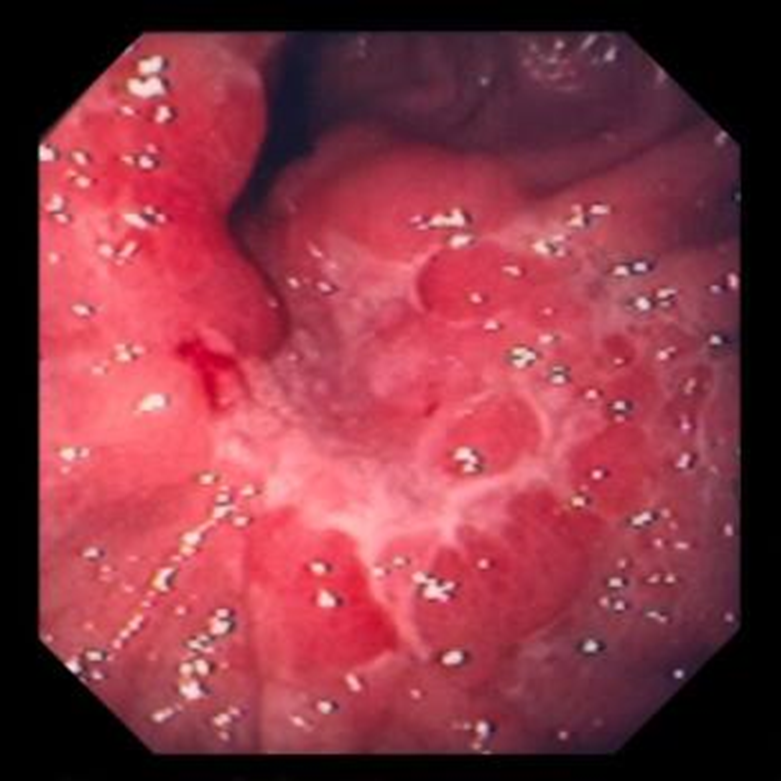

Ung thư dạ dày

Bệnh nhân nghi ngờ bị ung thư dạ dày nên có nội soi sinh thiết nhiều mảnh và làm tế bào học bàn chải. Đôi khi, sinh thiết giới hạn ở niêm mạc bỏ lỡ các mô khối u ở dưới niêm mạc. Chụp X-quang, đặc biệt là chụp x quang có barit đối quang kép, có thể cho thấy các tổn thương nhưng hiếm khi tránh được việc nội soi dạ dày sau đó.